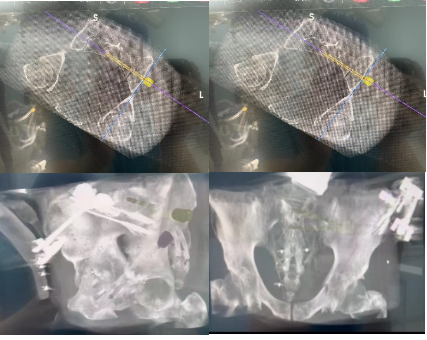

手术当天,骨科治疗组组长何罕亮副主任医师带领团队采用先进的二代臂机对患者进行骨盆图像采集,并将影像学资料上传至机器人计算机中。经过机器人的精密运算,患者的骨折三维图像非常直观地呈现在医生面前。随后,何主任团队根据图像实时进行手术规划,选择最佳置钉通道。手术机器人机械臂根据制定好的路线精准定位,将误差控制在1mm之内,使得医生不必扩大切口即可暴露骨折断端。只需3个毫米级切口,螺钉便可精准打入狭长的耻骨中,避免损伤重要的血管、神经组织。通道确定后,整个置钉过程短短几分钟便完成了,手术出血量不足10ml。精准的置钉操作使得医生不必担心反复调整所致的钉道松动,术后透视也进一步确认了螺钉位置准确无误,这预示着手术圆满成功。

机器人术中规划髋臼前柱螺钉&骨盆骶髂螺钉